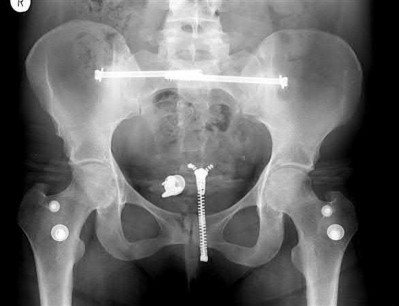

A 23-year-old female is an unrestrained driver in a motor vehicle collision, sustaining the injury shown in Figure A. She subsequently undergoes reduction and percutaneous bilateral iliosacral screw placement. Which of the following is the most likely neurologic complication associated with percutaneous iliosacral screw insertion?

Figure A shows an unstable bilateral pelvic ring injury. Percutaneous posterior iliosacral screw fixation places the L5 nerve root at risk as it courses across the sacral ala. Injury to the L5 nerve root would typically result in weakness in great toe extension and sensory changes on the dorsum of the foot. It is important to notice that L5 often partially innervates tibialis anterior along with L4, so weakness to ankle dorsiflexion may be present as well. Illustration A shows the post-operative films with bilateral iliosacral screws.

Routt et al examined the sacral slope and sacral alar anatomy in cadavers and a series of consecutive patients. They determined that the pelvic outlet and lateral sacral plain films provide the best plain radiographic views of the sacral ala. They recommended routine usage of these views intraoperatively to guide screw placement.

In another study, Routt et al reported on the early complications of percutaneous placement of iliosacral screws for treatment of posterior pelvic ring disruptions. While technically challenging, this technique leads to less blood loss and lower rates of infection compared to traditional open techniques.